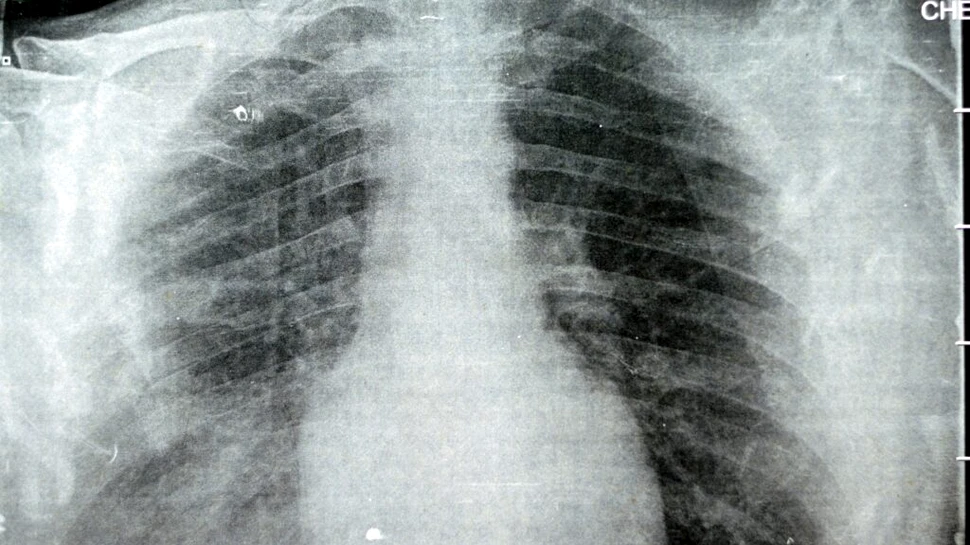

O formă rară de pneumonie, provocată de bacterii transmise prin instalațiile de aer condiționat, a omorât cinci oameni în SUA. Este concluzia la care au ajuns oficialii americani. Alte 14 persoane sunt în spital.

Cinci persoane au murit în cartierul Harlem din New York, iar 14 sunt spitalizate după ce au avut boala legionarilor (legioneloza), au anunțat oficialii din domeniul sănătății, potrivit Le Figaro.

În total, 108 cazuri au fost confirmate în cartier, a menționat Departamentul de Sănătate al orașului New York, adăugând că bacteria care provoacă boala a fost descoperită în instalațiilor de aer condiționat.

Legioneloza este o infecție pulmonară gravă, cu o rată de mortalitate de 9%. Contaminarea se poate face prin apă sau prin aer.